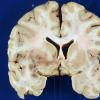

2B NMO Spectrum Disorder (Case 2) Gross